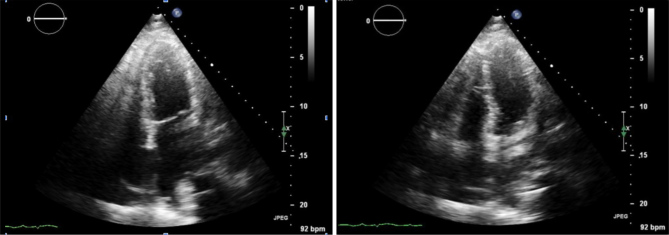

Minoxidil is a direct-acting vasodilator that reduces systemic vascular resistance by opening adenosine triphosphate (ATP)-sensitive potassium channels, leading to arteriolar smooth muscle vasodilation. While commonly prescribed for resistant hypertension and androgenic alopecia, minoxidil is associated with fluid retention, and in rare cases, pericardial effusion that can progress to cardiac tamponade. In this report, we present a case of an 81-year-old male with a history of chronic kidney disease (CKD) who developed cardiac tamponade while on chronic minoxidil therapy for hypertension. He presented with progressive dyspnoea, lower extremity oedema, and fever. Imaging revealed an enlarged cardiac silhouette, and a confirmatory echocardiogram demonstrated a pericardial effusion with right ventricular collapse. The patient underwent urgent pericardiocentesis, yielding 545 ml of pericardial fluid. Infectious, malignant, and autoimmune aetiologies were ruled out, and minoxidil was identified as the likely cause. Following discontinuation of minoxidil, the patient's symptoms completely resolved, with no recurrence at 1-month follow-up. In addition, we reviewed 26 previously reported cases of minoxidil-induced pericardial effusion and/or cardiac tamponade, 17 of which are summarized in this report. This case demonstrates the rare but potentially fatal complication of therapy and emphasizes the importance of early detection and clinical vigilance, particularly in vulnerable populations such as patients with CKD.

Abstract Image